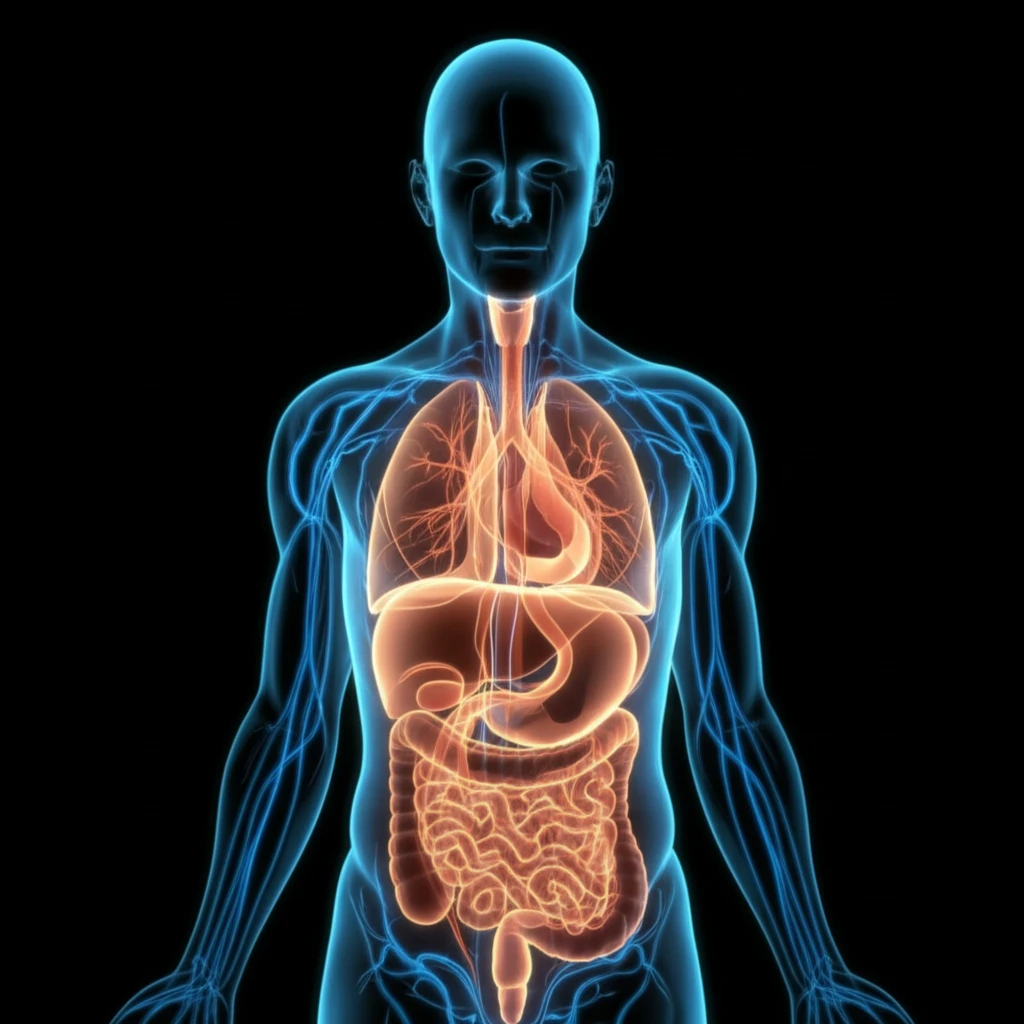

Cystic Fibrosis (CF) is a genetic disease primarily affecting the lungs and digestive system. It's caused by a defective gene that leads to a buildup of thick mucus in the body. This can lead to chronic respiratory infections, difficulty breathing, and problems with digestion. While often diagnosed in childhood, many individuals with CF are now living well into adulthood, thanks to advances in treatment and care.

Respiratory issues remain the leading cause of health problems for individuals with CF. The buildup of thick mucus in the lungs creates an environment ripe for bacterial infections and chronic inflammation. Let's break down some of the most common acute respiratory complications: